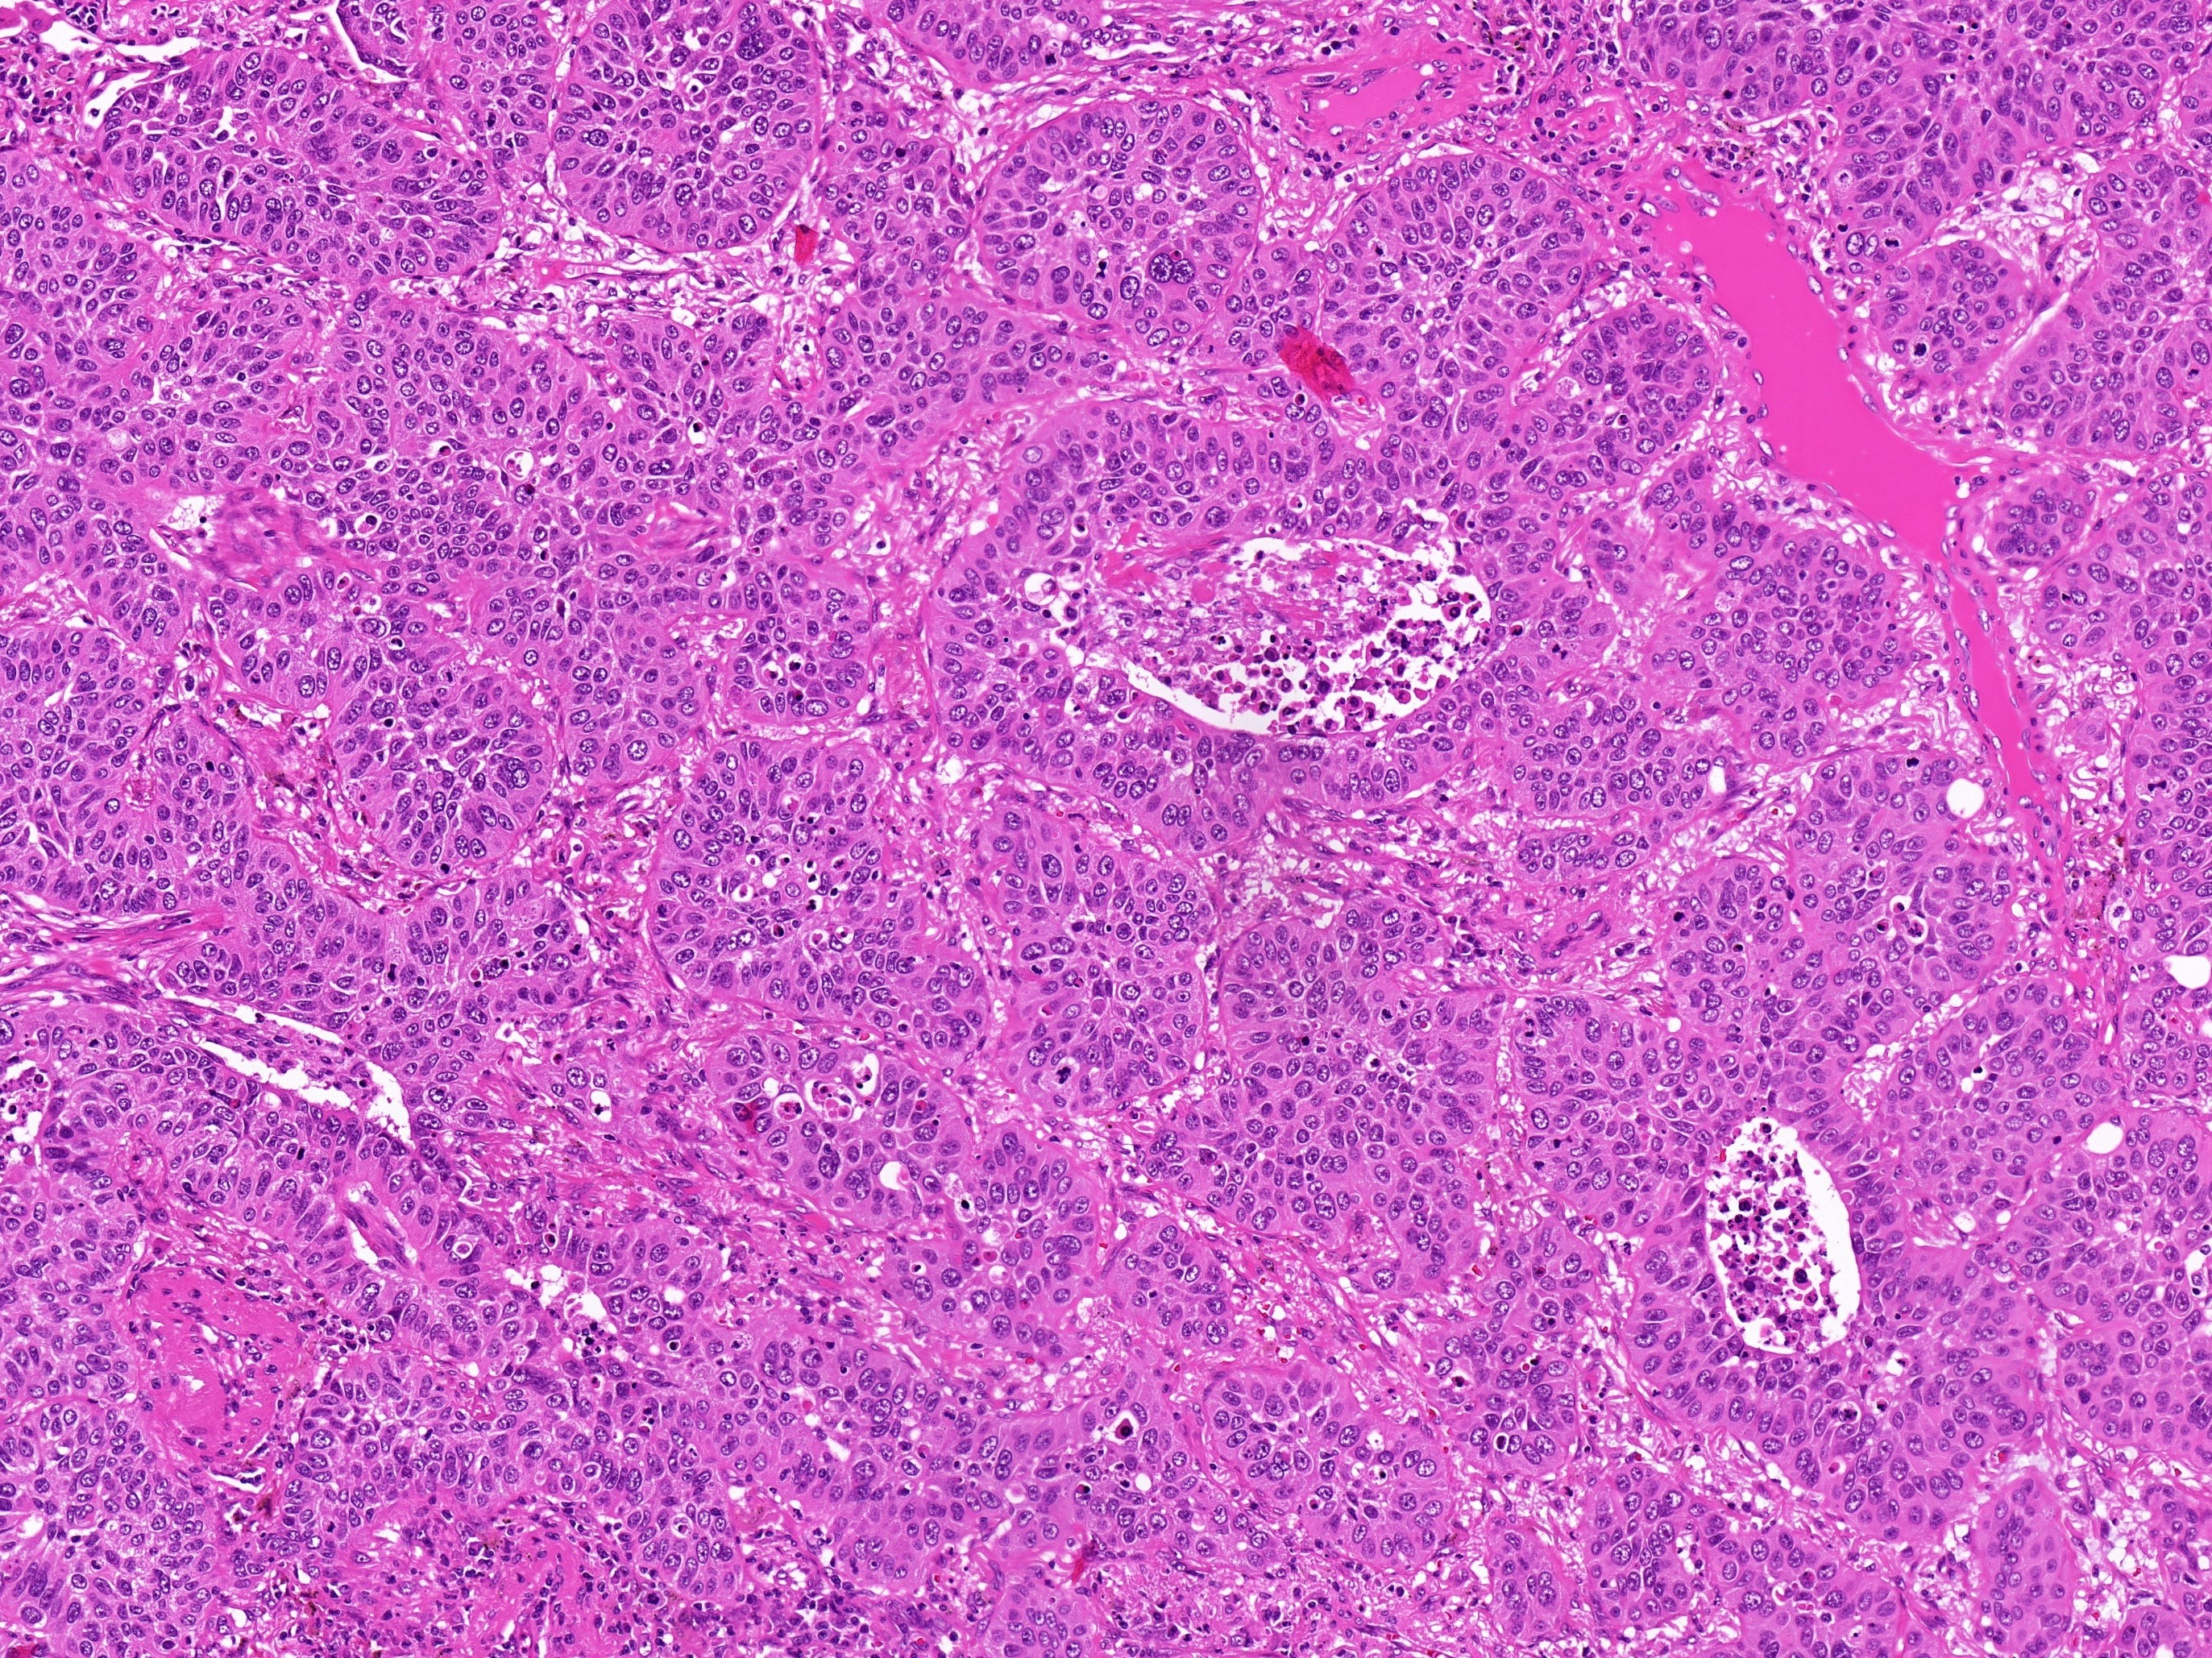

Normalerweise greifen Pathologen zur Unterscheidung zwischen Metastase und Zweittumor auf etablierte Methoden wie die Analyse der Feinstruktur des Tumors sowie den Nachweis charakteristischer Eiweiße im Gewebe zurück. Da Kopf-Hals-Tumoren und Lungenkarzinome hier jedoch große Ähnlichkeit zeigen, liefern diese Untersuchungen in einem Großteil der Fälle kein eindeutiges Ergebnis. „Um dieses Problem zu lösen, analysierten wir Gewebeproben hinsichtlich einer speziellen chemischen Veränderung der DNA, der sogenannten Methylierung“, erläutert Prof. Capper, der wie auch Prof. Klauschen wissenschaftliches Mitglied des DKTK am Standort Berlin ist. „Aus früheren Studien wissen wir, dass das Methylierungsmuster von Krebszellen sehr stark davon abhängig ist, aus welchem Organ der Tumor abstammt.“